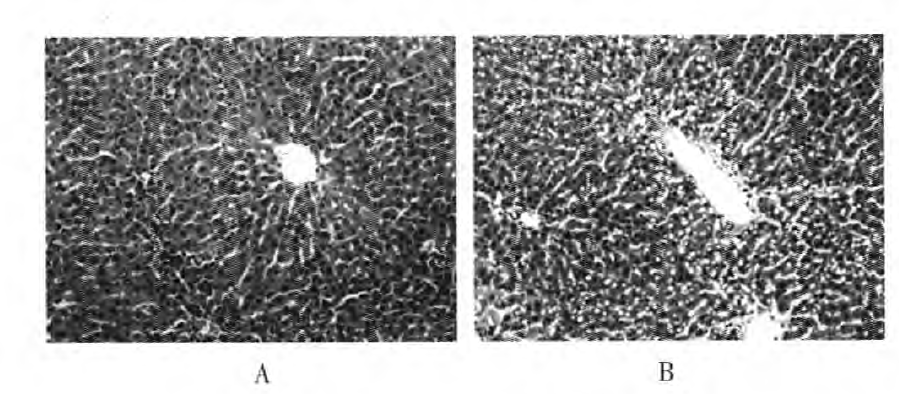

- 模型观察采样:在灌胃过程中和灌胃结束后,密切观察动物的行为学变化、体重变化、毛发色泽改变及精神状态等一般情况。每周称重,记录摄食量及精神状态;造模4周后禁食12 h,麻醉下心脏采血分离血清;取肝、脑组织,部分福尔马林固定(病理切片),部分液氮速冻(分子检测)。

鼠肝脏HE染色病理图(×200)

四、模型特点与应用

- 模型特点:乙醇灌胃诱导的慢性酒精中毒模型具有诱发因素明确、操作方法简便、实验重复性好等优点。同时,该模型能够较好地模拟人类长期过量饮酒导致的慢性酒精中毒状态,包括行为学改变、生理生化指标异常以及组织病理学改变等。